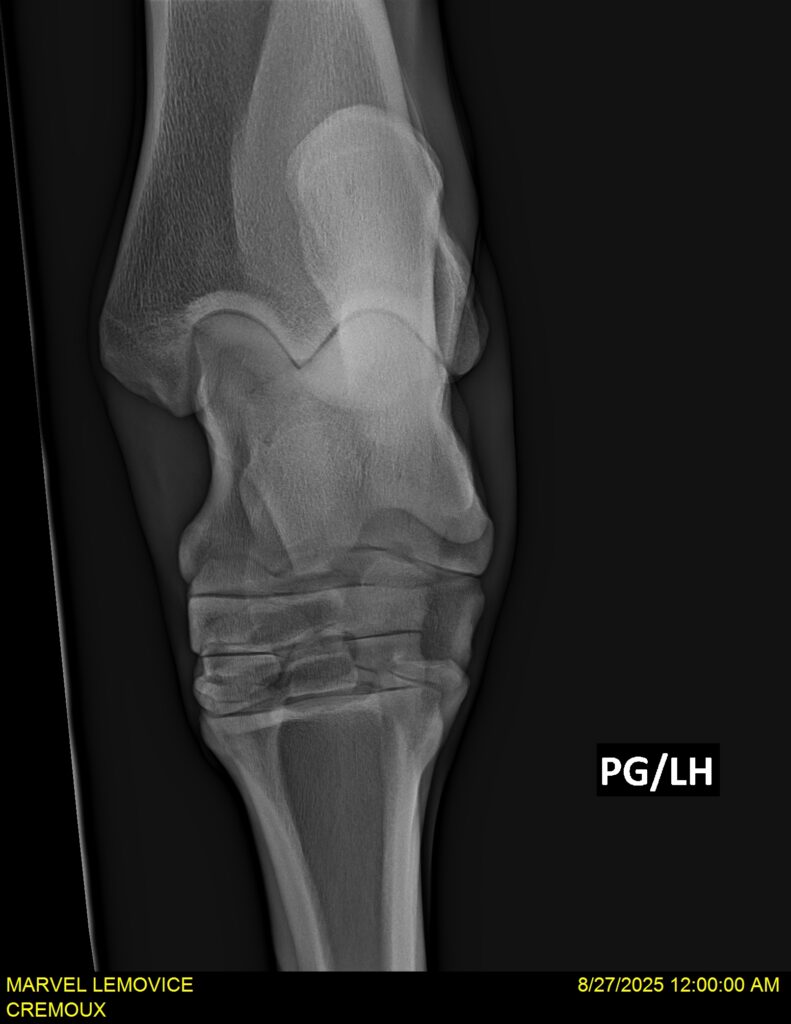

MARVEL LEMOVICE, hongre, Selle Français prend 4 ans en 2026. POPSTAR LOZONAIS x ROSIRE sur une excellente souche maternelle de l’élevage PLATIERE. Débourré aux trois allures et mise en route à l’obstacle. Super modèle avec du cadre et de la force, cheval respectueux avec des moyens. Très agréable au quotidien. Transport OK, maréchalerie OK, santé RAS, Bilan 20 clichés radios + clinique OK.

RADIOS ET CLINIQUE